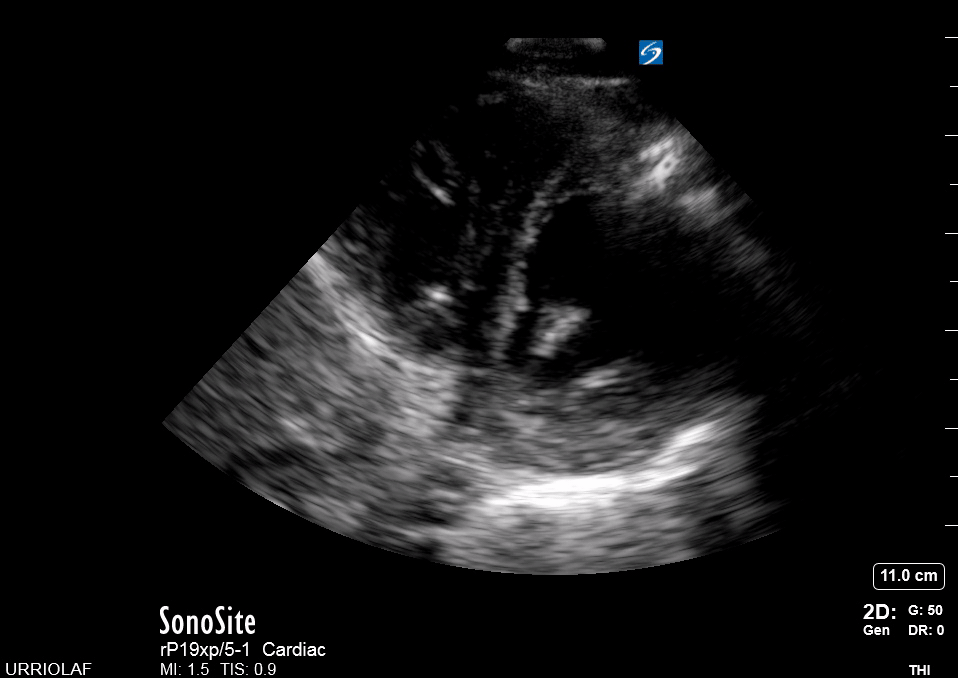

PLAX

PARASTERNAL LONG-AXIS VIEW

This is a versatile view and provides a considerable amount of information from different structures. It is useful to assess the left ventricle contractility, estimate the ejection fraction, and measure the aortic root size. It also gives insight into the chamber relationship (RV:AoRt:LA = 1:1:1) and differentiates pleural from pericardial effusion.

ORIENTATION & TECHNIQUE

The initial obstacle in obtaining a PLAX view is due to screen orientation in the cardiac preset. If the marking on the screen is on the right side, the marking on the probe should point to the right shoulder. If for any reason, the marking on the screen is on the left side, then the marking on the probe should point to the left hip. Either way, the probe will always follow the long axis and have the proper orientation.

Place the transducer at the level of the second to fourth left intercostal space. Scoping around this area will eventually reveal a pulsatile motion. After finding the heart, adjust the depth to include the descending aorta. Slightly rotate and fan the probe until it aligns with the heart’s long axis. Importantly, such alignment will provide an accurate sagittal view, avoiding oblique views that could overestimate or underestimate the size of the chambers.

LANDMARKS

A correct PLAX view will align with the heart’s long axis, producing a sagittal cut. On the screen, from the top, we see the right ventricle, the interventricular septum, the left ventricle with its outflow tract, the aortic valve and aortic root, and the left atrium. It is essential to look for the descending aorta, which appears in a transversal cut deeper to the LV.